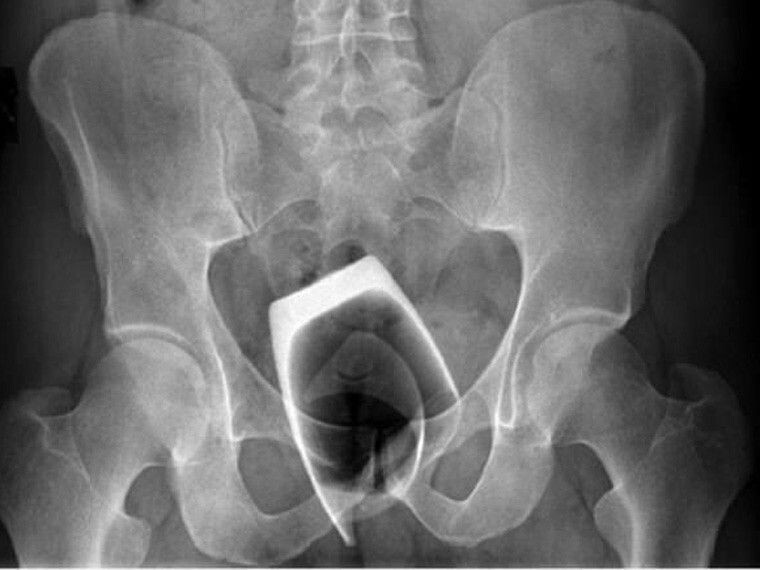

Доктор сразу же отправил его на рентген, на котором врачи увидели не стаканчик как выразился молодой человек, а гранёный стакан, который был засунут в заднепроходное отверстие донышком вниз. И как мне объяснили: когда стакан туда попал вытащить оттуда его было крайне трудно, попа его поглотила и так как стенки стакана не давали выйти ему природным способом и он застрял.

Доктор позвонил главврачу для консультации. Было принято решение ввести пациенту наркоз и под ним извлечь стакан из попы. Парня усыпили и начали вытаскивать стакан, как я понял какими-то пассатижами или чем-то вроде этого. Зацепили его и начали пытаться вытащить, но стакан начал трескаться. Хирургам пришлось разрезать живот и вытащить стакан через брюшная полость. Через несколько дней его выписали, с ним всё хорошо. Мораль такого не суйте в попу всё подряд 😁